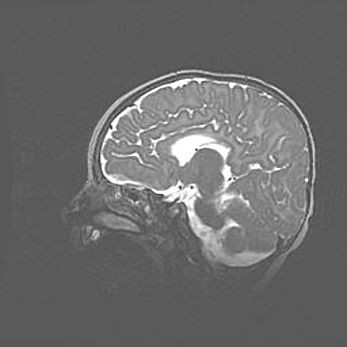

Мальформация Денди-Уокера. Киста задней черепной ямки.

Агенезия мозолистого тела.

Возраст: 2,5 месяца

Вес: 2420 г

Пол: женский

Окружность головы: 37 см

Срок гестации: 32 недели

Мальформация Денди—Уокера — редкий вид патологии ЦНС, представляющий собой врожденный порок развития каудального отдела ствола и червя мозжечка, ведущий к неполному раскрытию срединной (Мажанди) и латеральных (Лушка) апертур IV желудочка мозга. Для этогно синдрома характерна триада симптомов: гипотрофия червя мозжечка и/или полушарий мозжечка, кисты задней черепной ямки, гидроцефалия различной степени. В 70% случаев порок сочетается и с другими аномалиями головного мозга, в частности с агенезией мозолистого тела.